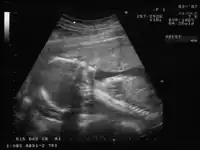

Ecografía de un feto de 20 semanas, fecha para la cual empiezan a aparecer los signos preeclámpticos.

Se diagnostica la preeclampsia cuando en una mujer embarazada aparece repentinamente una elevación de la presión arterial —en dos lecturas separadas tomadas al menos 6 horas aparte de 140/90 mmHg o más— y un nivel de proteína en la orina de 300 mg o más. Una elevación de la presión arterial de 20 mmHg del valor sistólico (el valor más alto) y de 15 mmHg del valor diastólico (el valor más bajo), aunque no llegue al requerimiento de 140/90, es considerado de importancia aunque ya no se considera diagnóstico. Originalmente se consideraba que las hinchazones —edema, especialmente de las manos y cara— eran signos de importancia diagnóstica de la preeclampsia, pero la práctica médica actual solo la hipertensión y la proteinuria son requeridos para el diagnóstico. A pesar de ello, las hinchazones inusuales, en particular en las manos, pies o cara, apreciables al dejar una indentación al presionar el área en cuestión, debe ser considerado significativo y reportado al profesional de salud. Algunas madres con preeclampsia tienen una especial tendencia a la agregación plaquetaria y a elevados niveles de serotonina séricos.[17]